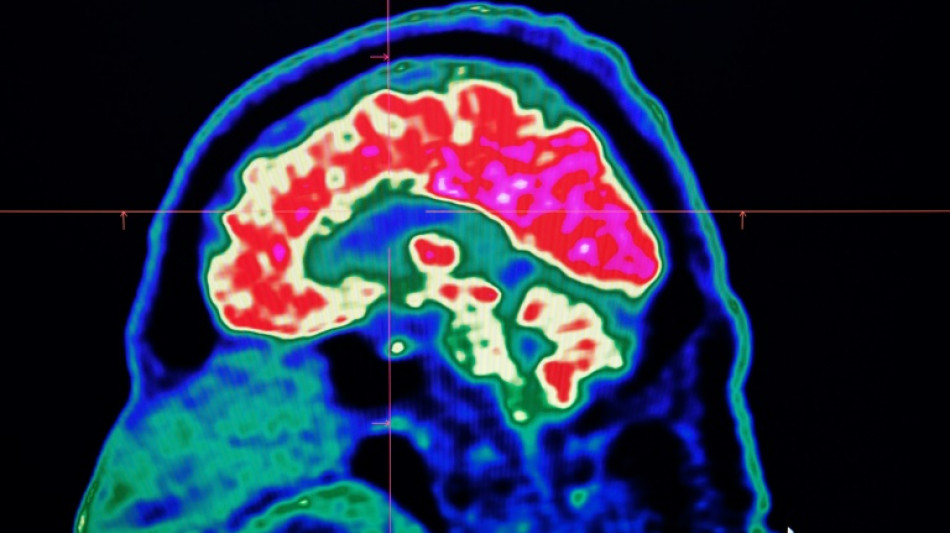

Tiny shards of plastic called microplastics have been detected accumulating in human brains, but there is not yet enough evidence to say whether this is doing us harm, experts have said.

These mostly invisible pieces of plastic have been found everywhere from the top of mountains to the bottom of oceans, in the air we breathe and the food we eat. They have also been discovered riddled throughout human bodies, inside lungs, hearts, placentas and even crossing the blood-brain barrier.

The most prominent study looking at microplastics in brains was published in the journal Nature Medicine in February.

The scientists tested brain tissue from 28 people who died in 2016 and 24 who died last year in the US state of New Mexico, finding that the amount of microplastics in the samples increased over time.

The study made headlines around the world when the lead researcher, US toxicologist Matthew Campen, told the media that they detected the equivalent of a plastic spoon's worth of microplastics in the brains.

Campen also told Nature that he estimated the researchers could isolate around 10 grammes of plastic from a donated human brain -- comparing that amount to an unused crayon.